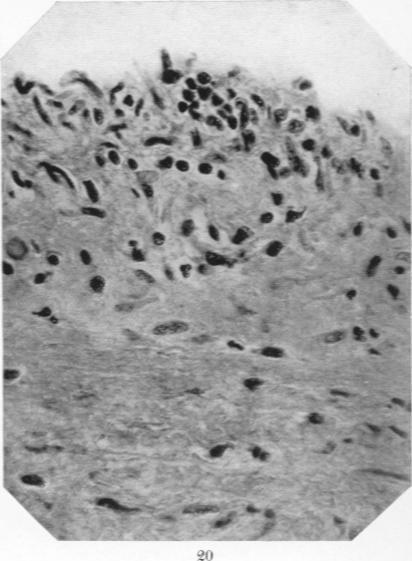

Studies in the Pathology of Rheumatic Fever: Two Cases Presenting unusual Cardiovascular Lesions.

Am J Pathol. 1927 Nov;3(6):583-594.19.